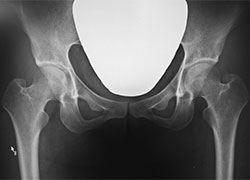

増原クリニックは股関節疾患専門のクリニックであり、基本的に股関節に不具合をお持ちの方を中心に診療を行っております。

股関節の障害であっても、腰や膝など他の部位に痛みが生じることもあります。股関節専門医としての豊富な経験をもとに的確に診断、治療いたします。ご自分で判断せずに専門医にご相談ください。